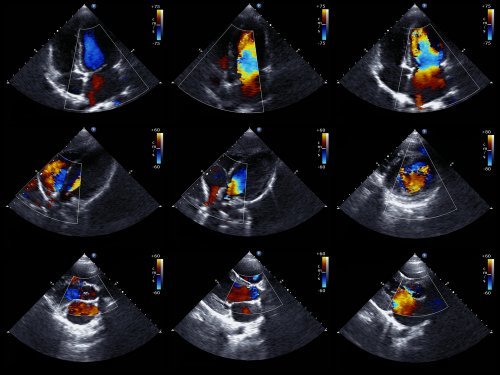

L’ecocardiogramma è un esame medico ampiamente utilizzato, poiché consente di ottenere immagini in movimento del cuore. In questo modo si può valutare lo stato delle camere cardiache e il loro movimento, e quindi confermare o escludere l’ischemia.

Si possono valutare anche la dimensione del cuore, la sua forza e lo stato delle pareti che definiscono le sue camere. È un esame non invasivo, che non comporta rischi per il paziente. Questo perché utilizza gli ultrasuoni per ottenere le immagini dell’organo.

L’assenza di alterazioni nella mobilità delle pareti cardiache esclude la presenza di ischemie. D’altra parte, tali anomalie non è sono esclusive della sindrome coronarica acuta. Per questo motivo, i risultati degli esami e i sintomi devono essere valutati nel dettaglio insieme al medico.